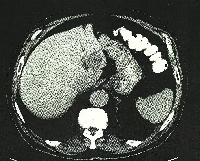

Πρόκειται για άνδρα ασθενή 80 ετών ο οποίος, στα πλαίσια διερεύνησης μικροκυτταρικής αναιμίας, διαπιστώθηκε ότι έπασχε από αδενοκαρκίνωμα του τυφλού. Η σταδιοποίηση που ακολούθησε ανέδειξε μονήρη ηπατική μετάσταση μεγέθους 4 cm (εικόνα 1). Ο ασθενής υποβλήθηκε σε σύγχρονη αριστερή πλάγια ηπατεκτομή (εικόνα 2) και δεξιά κολεκτομή (εικόνα 3). Η ιστοπαθολογική εκτίμηση των παρασκευασμάτων (εικόνα 4) επιβεβαίωσε τη διάγνωση. Έλαβε εξιτήριο την 5η μετεγχειρητική ημέρα. Ακολούθως, υποβλήθηκε σε 12 κύκλους μετεγχειρητικής χημειοθεραπείας (XELOX, Avastin). Eξακολουθεί να παραμένει ελεύθερος νόσου.